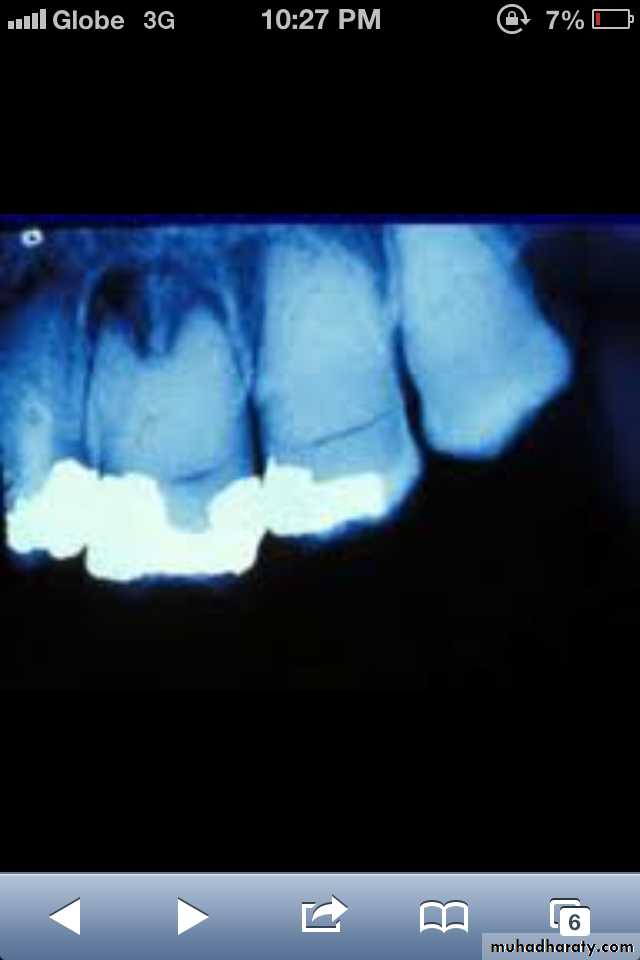

Dentin dysplasia, type II. panoramic &periapical films of the same case show obliteration of the pulp chamber, reduction in the caliber of root canals, and pulp stones obscuring the flame-shaped pulp chambers.

Periapical inflammatory lesions are associated with some of the mandibular anterior teeth.